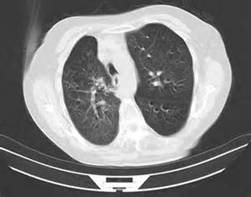

(3)胸部X线检查:慢阻肺早期X线胸片可无明显变化,以后出现肺纹理增多和紊乱等非特征性改变;主要X线征象为肺过度充气:肺容积增大,胸腔前后径增长,肋骨走向变平,肺野透亮度增高,横膈位置低平,心脏悬垂狭长,有时可见肺大疱形成。

COPD患者影像学改变